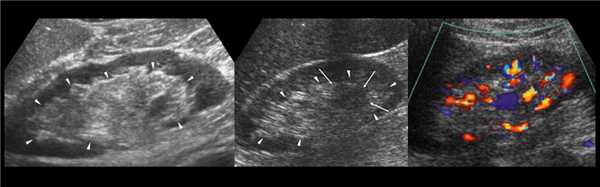

Клинический пример из первой группы. Пациент М., с хронической почечной недостаточностью. Трансплантация почки произведена от живого родственного донора. Трансплантат находится в правой подвздошной области. При нормальном функциональном состоянии трансплантата, показатели цветовой и спектральной допплерографии оценивались как удовлетворительные, с индексом резистентности не более 0,60 (рис. 1); показатели жесткости паренхимы почечного трансплантата при УЭСВ на различных участках составили от 20,05 до 29,18 кПа (рис. 2-4).

Рисунок 2. Исследование в режиме ультразвуковой эластографии сдвиговой волны у пациента М.: жесткость паренхимы в зоне медиального края трансплантата 19,8 кПа

Рисунок 3. Исследование в режиме ультразвуковой эластографии сдвиговой волны у пациента М.: жесткость паренхимы в зоне верхнего полюса почечного трансплантата 21,4 кПа

Рисунок 4. Исследование в режиме ультразвуковой эластографии сдвиговой волны у пациента М.: жесткость паренхимы в зоне нижнего полюса почечного трансплантата 16,8 кПа

У пациентов второй группы, при нормальных показателях клинико-лабораторных и допплерографических исследований, показатели жесткости почечного трансплантата составили 17,00-26,06 кПа.

Клинический пример из второй группы. Пациент К. перенес операцию пересадки почки от живого родственного донора. Трансплантат в левой подвздошной области. Индекс резистентности в междольковых артериях составил 0,70 (рис. 5). В сегментарных артериях индекс резистентности составил 0,66 (рис. 6). Показатели жесткости паренхимы почечного трансплантата при режиме УЭСВ составили от 31,6 до 36,9 кПа (рис. 7-9).

Рисунок 7. Исследование в режиме ультразвуковой эластографии сдвиговой волны у пациента К.: жесткость паренхимы в зоне медиального края почечного трансплантата 36,9 кПа

Рисунок 8. Исследование в режиме ультразвуковой эластографии сдвиговой волны у пациента К.: жесткость паренхимы в зоне нижнего полюса почечного трансплантата 34,7 кПа

Рисунок 9. Исследование в режиме ультразвуковой эластографии сдвиговой волны у пациента К.: жесткость паренхимы у верхнего полюса почечного трансплантата 31,6 кПа

При снижении скорости кровотока и повышении индекса резистентности до 0,70 и более, как в первой, так и во второй группах, показатели УЭСВ составили от 28,00 до 39,45 кПа. Повышение жесткости паренхимы почечного трансплантата, на наш взгляд, связано с начавшимися изменениями (фиброза) в паренхиме почки. При повышении индекса резистентности более 0,70 показатели жесткости паренхимы при УЭСВ является дополнительным критерием, позволяющим оценить функциональное состояние почечного трансплантата. Ультразвуковая эластография ― новая развивающаяся методика, чувствительность, специфичность и точность которой увеличиваются при комплексном использовании с другими методами исследования. Анализ результатов проведенных исследований выявил значительные клинические возможности и перспективы применения метода ультразвуковой эластографии сдвиговой волны в оценке состояния почечного трансплантата. Полученные данные о диагностической точности метода позволяют использовать результаты в целях принятия решения о дальнейшем ведении пациента и тактике лечения [4].